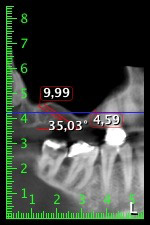

About six months after teeth 16 and 14 were extracted, a digital volume tomography (DVT, Planmeca) examination was performed for planning and risk minimization purposes. It clearly showed that the bone had not regenerated to the desired volume (Fig. 2 to 7).

Image 2 to 7: DVT with greatly reduced horizontal bone volume.